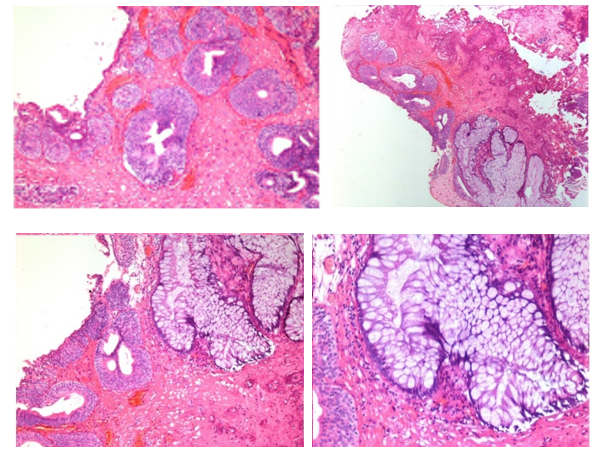

An abdominal ultrasound revealed a polypoidal growth measuring approximately 5.0 x 2.7 x 2.1 cm arising from the base of the urinary bladder, with marked vascularity observed on power Doppler. Subsequently, a contrast-enhanced CT scan of the abdomen and pelvis confirmed the presence of a markedly enhancing, homogeneous polypoidal soft tissue mass, measuring about 5.1 x 2.8 x 2.2 cm, arising from the base of the urinary bladder. (Figure 1)

Figure 1 Contrast enhanced CT images of urinary bladder Axial (A) Sagittal (B) and Coronal (C) showing polypoidal enhancing mass arising from base of urinary bladder.